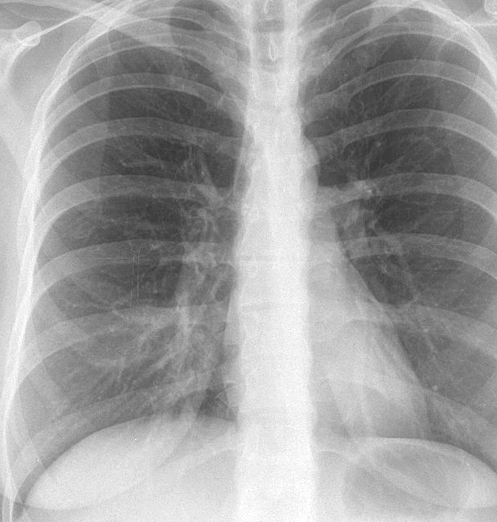

Case 5 RML med seg PA